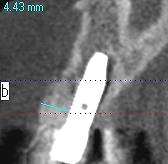

頬側は骨造成をしています頬側は

頬側は骨が3mm以上ないといけません

将来的に周囲の歯が無くなっても安定した位置への埋入

になっているかと思います